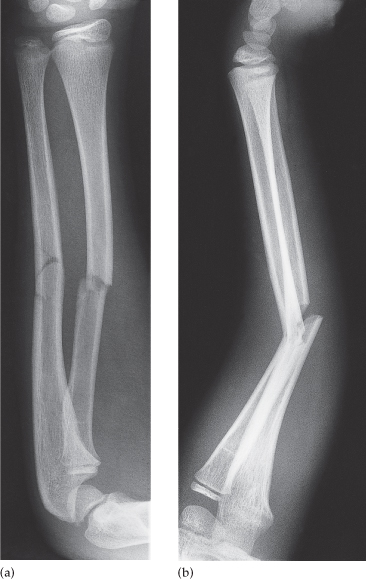

Traumatic Fracture

Trauma and Fractures | OASIS Orthopaedics Melbourne Traumatic Injury & Fracture Treatment - My Toronto Physio Traumatic Spine Fracture - Goodman Campbell All Types of Fractures & Trauma - Dr. Prajaktam Lende's Niva Ortho Care | Orthopedic Surgeon In Nagpur | Orthopedic Doctor in Nagpur | Traumatic Fracture